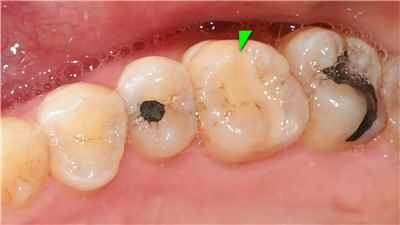

치아 변색 외부 요인